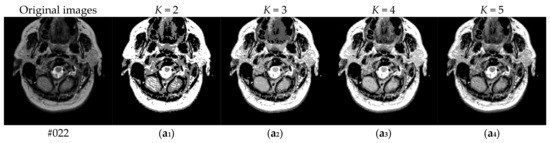

To verify the performance of the proposed algorithm, five representative multi-threshold segmentation algorithms are selected for comparative experiments. The five comparative experimental algorithms are: (1) image threshold segmentation algorithm based on particle swarm optimization (PSO), (2) image threshold segmentation algorithm based on bacterial foraging (BF), (3) image threshold segmentation algorithm based on adaptive bacterial foraging (ABF), (4) image threshold segmentation algorithm based on Nelder-Mead simplex (NMS), (5) image multi-threshold segmentation algorithm based on real coded genetic algorithm (RCGA) [43]. The number of thresholds is set to K = 2, 3, 4, and 5, respectively. Due to the limited space, we only show the segmentation results of the proposed algorithm in this paper. Figure 8 shows the segmentation results of Slice#022~#112 when the threshold K = 2, 3, 4, 5. Intuitively, the proposed algorithm can better segment each region of the experimental image, and the continuity of different regions is well guaranteed. At the same time, the visual effects are satisfactory.

Figure 8.

Segmentation results obtained by the proposed algorithm for brain slices #022~#112; (a1–j1) display the results of 2-thresholding; (a2–j2) display the results of 3-thresholding; and (a3–j3) display the results of 4-thresholding; (a4–j4) display the results of 5-thresholding.